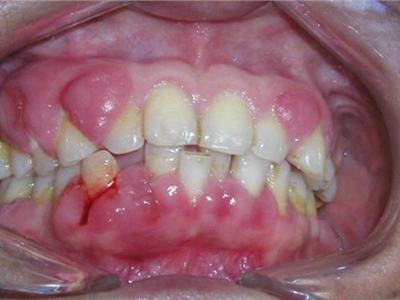

牙龈炎是发生于牙龈组织的炎症,患者可出现牙龈出血伴肿胀、发红、正常形态改变和偶尔不适等症状。本病主要由口腔卫生状况差导致,包括口腔不洁、牙菌斑等,诊断依据临床检查,治疗包括专业牙齿清洁和加强家庭口腔卫生。

牙龈炎可先引起牙齿与牙龈之间的沟(龈沟)加深,然后牙龈充血,炎症围绕一个或多个牙齿,伴牙龈乳头肿胀和易出血。一般无痛,可自行消退,也可维持轻度炎症数年。